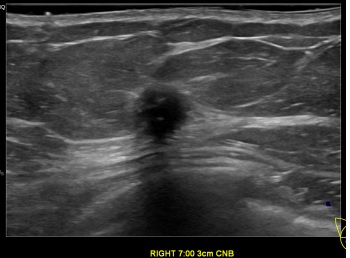

상기환자는 외부검진이상소견  정밀검사위해 내원하신 50대 중반

여성분으로 의심스러운 우측유방혹 조직검사 시행해 유방암으로 진단되었습니다.